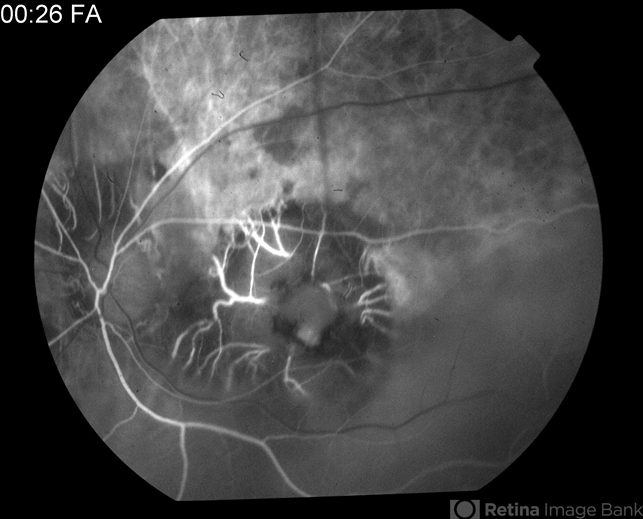

- tuberculosis, macular scar

- 0:26 second FA of 81-year-old male - old tuberculosis scar.